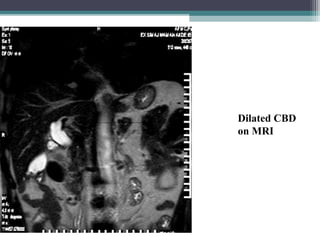

MAGNETIC RESONANCE CHOLANGIO-

PANCREATOGRAPHY (MRCP)

Normal anatomy

Dilated CBD

on MRI

Dilated IHBR and

CBD on MRCP